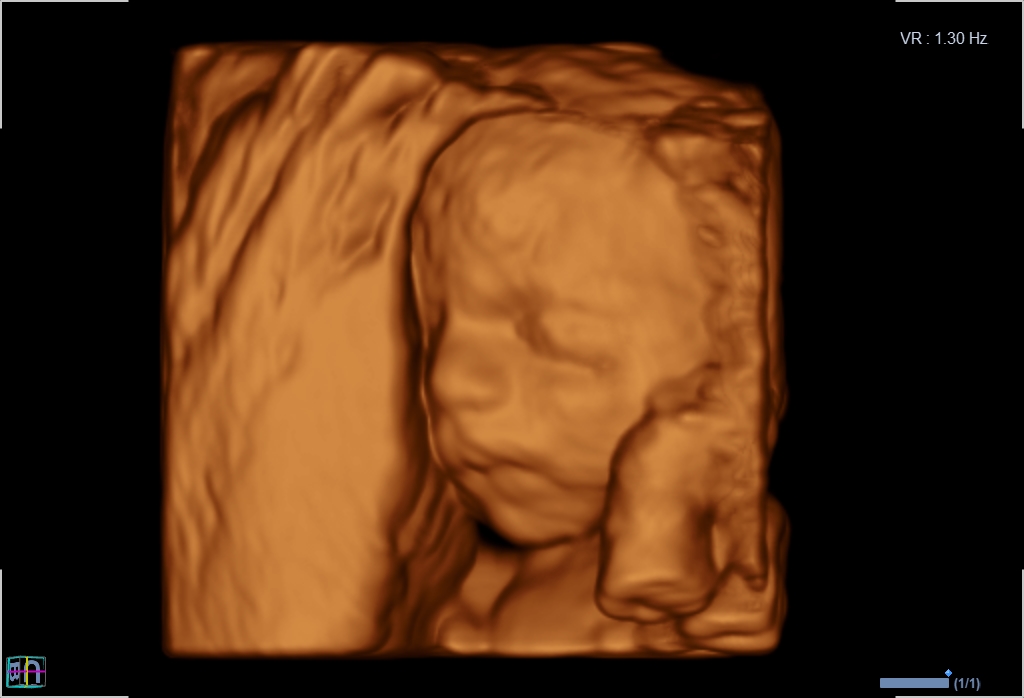

Seit März 2019 steht ein neues 3D/4D-Ultraschallgerät für faszinierende Eindrücke von Ihrem Baby zur Verfügung.

Außer den Fotos können auch 3D/4D Viedeoclips gemacht und auf einem USB-Stick gespeichert werden. So können die Bilder und Clips jederzeit angesehen werden.